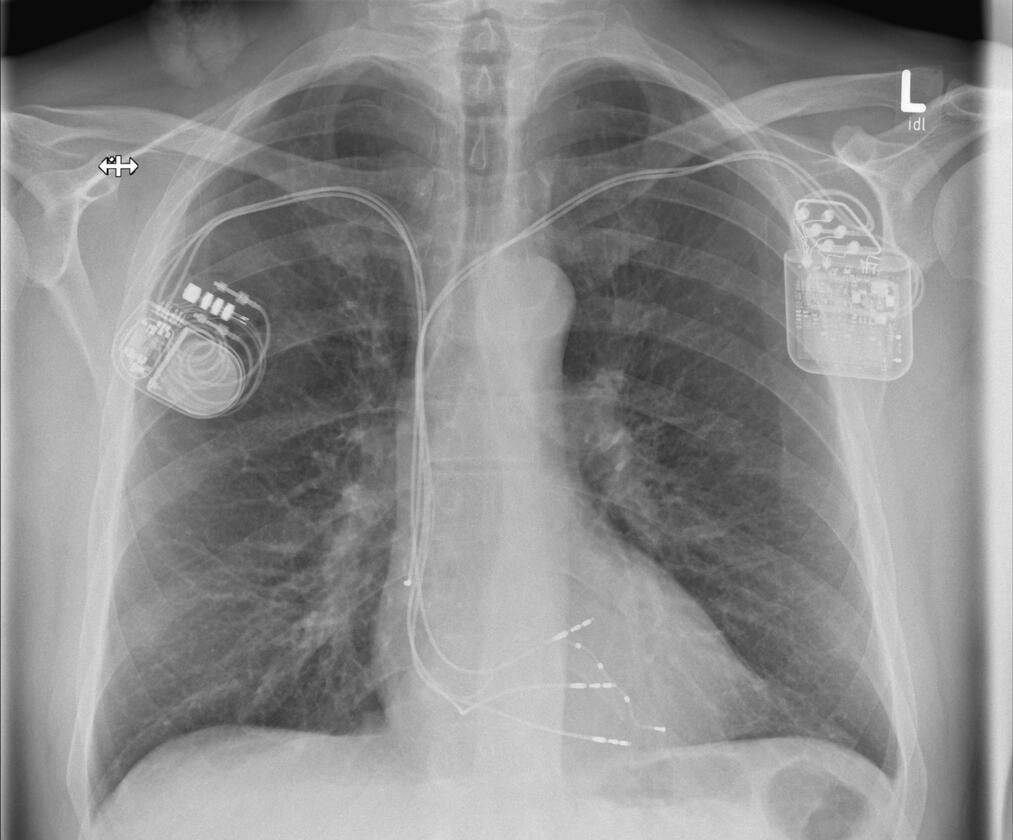

Wenn das Herz zu langsam schlägt, dann spricht man von einer Bradykardie. Diese ist meistens behandlungsbedürftig, denn sie kann zu Ohnmachtsanfällen (Synkopen) und im schlimmsten Fall zu einem Herzstillstand führen. Wenn sich keine behebbare Ursache finden lässt, ist die Implantation eines Herzschrittmachers die Therapie der Wahl. Der Schrittmacher regt den Herzmuskel mit leichten nicht spürbaren elektrischen Impulsen zum regelmäßigen Schlagen an. Der Herzschrittmacher wird in der Regel im Brustbereich unterhalb des Schlüsselbeines eingesetzt. Der kleine Eingriff erfolgt unter lokaler Betäubung während eines kurzen stationären Aufenthaltes oder auch ambulant. In unserer Klinik werden alle gängigen Systeme implantiert. Gerne informieren wir Sie in unserer Sprechstunde über weitere Einzelheiten. Hier erfolgt auf Wunsch auch die Nachsorge der implantierten Geräte (Sprechstunde).

Defibrillator

Die Implantation eines Defibrillators (ICD) erfolgt in der Regel bei einem erhöhten Risiko für gefährliche Herzrhythmusstörungen oder nach einem überlebten plötzlichen Herztod (SCD). Ein elektrischer Schock sorgt beim Auftreten einer entsprechenden Rhythmusstörung dafür, dass ein aus dem Takt geratenes Herz wieder richtig schlägt und die lebensbedrohliche Situation beendet wird. Die allermeisten Defibrillatoren haben zusätzlich die Funktion eines Herzschrittmachers. Ähnlich wie ein Herzschrittmacher wird das ICD-Gerät im Brustbereich unterhalb des Schlüsselbeines unter lokaler Betäubung eingesetzt. In unserer Klinik werden alle gängigen Systeme implantiert. Gerne informieren wir Sie in unserer Sprechstunde über weitere Einzelheiten. Hier erfolgt auf Wunsch auch die Nachsorge der implantierten Geräte (Sprechstunde).

Bei einer Herzmuskelschwäche pumpt der Herzmuskel häufig nicht mehr synchron. Aus diesem Grund kann es sinnvoll sein, diese „Asynchronie“ durch die Implantation zusätzlicher Stimulationssonden wieder zu beheben. Diese Sonden können die linke Herzkammer, aber auch direkt das Reizleitungssystem stimulieren. Eine solche kardiale Resynchronisationstherapie kann als reine Herzschrittmacherimplantation, aber auch in Kombination mit einem Defibrillator erfolgen. Grundsätzlich läuft die Operation wie die Implantation eines Herzschrittmachers ab, kann jedoch aufgrund der zusätzlichen Sonde(n) etwas länger dauern.